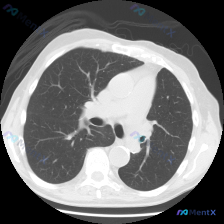

看到一份胸部CT肺窗横断面的病例资料,整理了一下分析思路,大家也可以一起看看。 主诉: 无症状体检发现肺部异常 现病史: 患者无明显咳嗽、咳痰、发热、盗汗等症状,体检行胸部CT检查发现右肺上叶后段有一处异常密度影。 关键检查/检验: 胸部CT肺窗显示右肺上叶后段靠近脊柱旁及纵隔旁区域有一类圆形实性结...